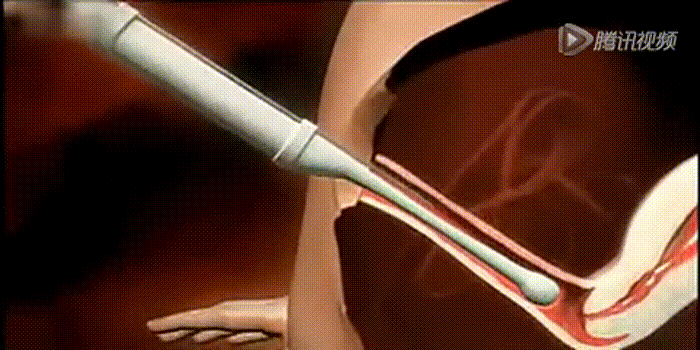

6胚胎移植

受精卵可在体外培养3-6天。此时依据病人的年龄、曾经怀孕与否及胚胎的质量,决定移植胚胎的数目,通常移植1-2个胚胎,多余的胚胎可冷冻保存。胚胎移植不需麻醉,没有疼痛。

随着体外培养条件的进步,胚胎可以在体外培养到囊胚阶段。推迟胚胎移植的时间,对体外培养的条件要求非常高,可通过筛选淘汰发育潜能不佳的胚胎,提高妊娠率,降低多胎率。